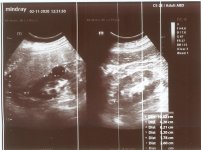

- استشاري موجات صوتية Fatty liver although normal size + Bilateral AKI more evidence in Rtside